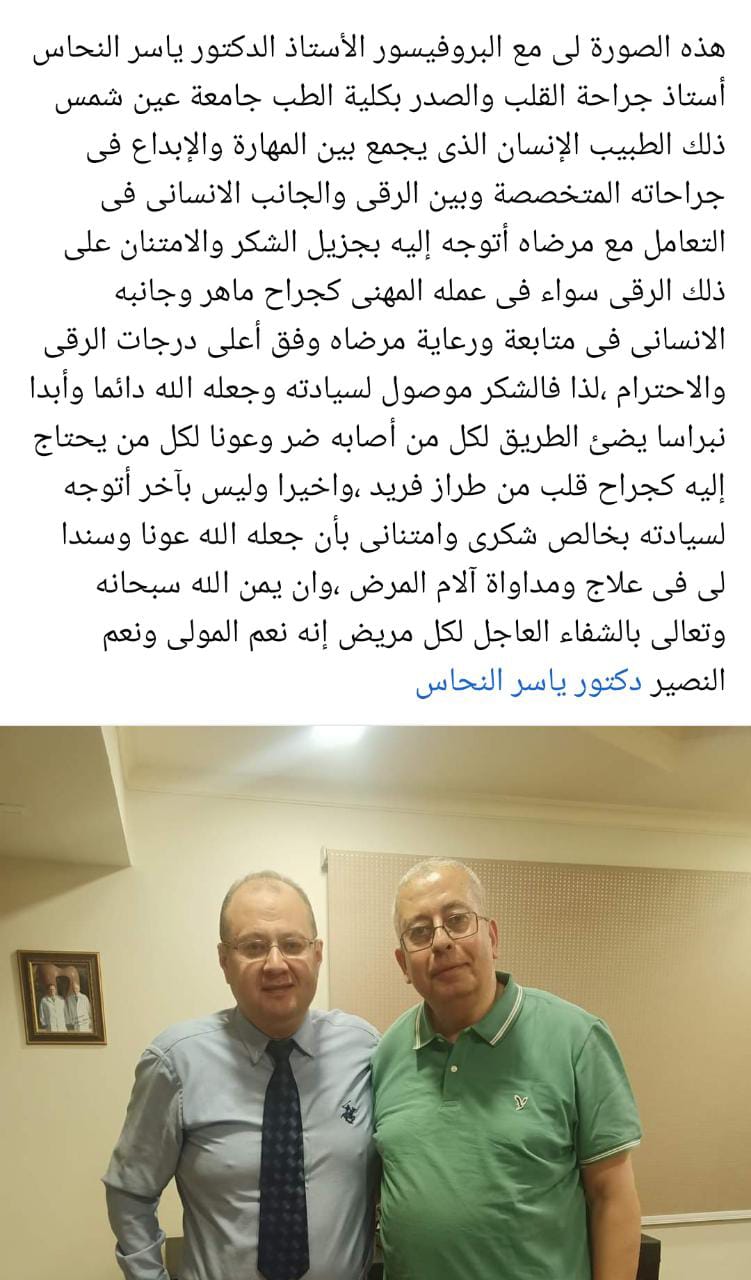

تشرفنا بكم

شكرا جزيلا